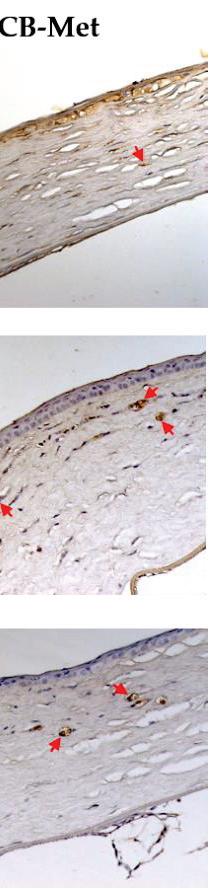

Duetotheanti-inflammatoryeffectintheCB-HexandtheCB-Met,weassessedwhetheritwas relatedtoanattenuationofCNV,bydeterminingthestainingintensityofVEGF-Aanditsreceptors (Figure 4).IntheCB-Veh,VEGF-Awasinthecytoplasmandnucleusoftheepithelial,endothelial, andotherinfiltratedcellswithanintensityof102.02 ± 14.04.AdecreaseinVEGF-Aintensitieswas observedfortheCB-Hex(71 ± 9.11)andCB-Met(61.3 ± 9.59)(p < 0.001)groups.Besides,staining intensitybetweenVEGF-AintheCB-MetandCB-Hexgroupsshoweddifferences(p < 0.05),andin thenon-CBgroupitwasabout16.25 ± 5.25(Figure 4a).The Vegf-a expressionwasalsoconfirmed (Figure 3c).The Vegf-a fortheCB-Hex(2.74 ± 0.34)andCB-Met(2.29 ± 0.23)groupsdecreasedcompared totheCB-Veh(4.40 ± 0.34; p < 0.05and p < 0.01,respectively).

Relevantly,stainingforVEGFR1wasdistributedinendothelialandinflammatorycellsofthe CB-Vehcorneas(54.4 ± 6.8)andwashigherwhencomparedtotheCB-Hex(33.13 ± 5.8; p < 0.0001) andCB-Met(25.47 ± 3.7; p < 0.0001)groups(Figure 4b).Vascularendothelialgrowthfactorreceptor 2immunostainingwaslocalizedinthemembraneregioninendothelialcells,andintheCB-Veh (23.06 ± 3.5)itwashighercomparedtotheCB-Hex(15.67 ± 2.6; p < 0.0001)andtheCB-Met(10.95 ± 2.1; p < 0.0001)groups(Figure 4c).

Figure4. ImmunolocalizationofvascularendothelialgrowthfactorA(VEGF-A)anditsreceptors, (vascularendothelialgrowthfactorreceptor1,VEGFR1,and-receptor2,VEGFR2),inthetreated groups.(a)StainingintensitiesforVEGF-A.(b)and(c)Membranousstaininginendothelialcellsfor VEGFR1andVEGFR2,respectively(redarrows).Redarrowsrepresentstainingintensityconsidered forsoftwareanalysis.(Scalebar = 100 μm).CB:chemicallyburnedcorneas;CB-Veh:CBcorneastreated withthevehicle;CB-Hex:CBcorneastreatedwithhexanicextract;CB-Met:CBcorneastreatedwith methanolicextract.